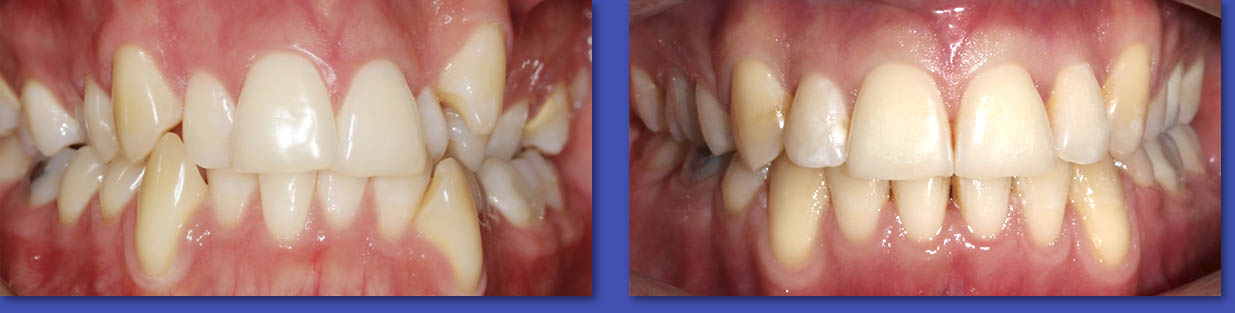

4. ORTODONCIA

La Ortodoncia se encarga del tratamiento de las anomalías de forma,posición,relación y función de las estructuras dentomaxilofaciales. La causa más común para el uso de aparatos de ortodoncia son las malposiciones dentarias o “ dientes chuecos “.

Ortodoncia

ANTES

DESPUÉS